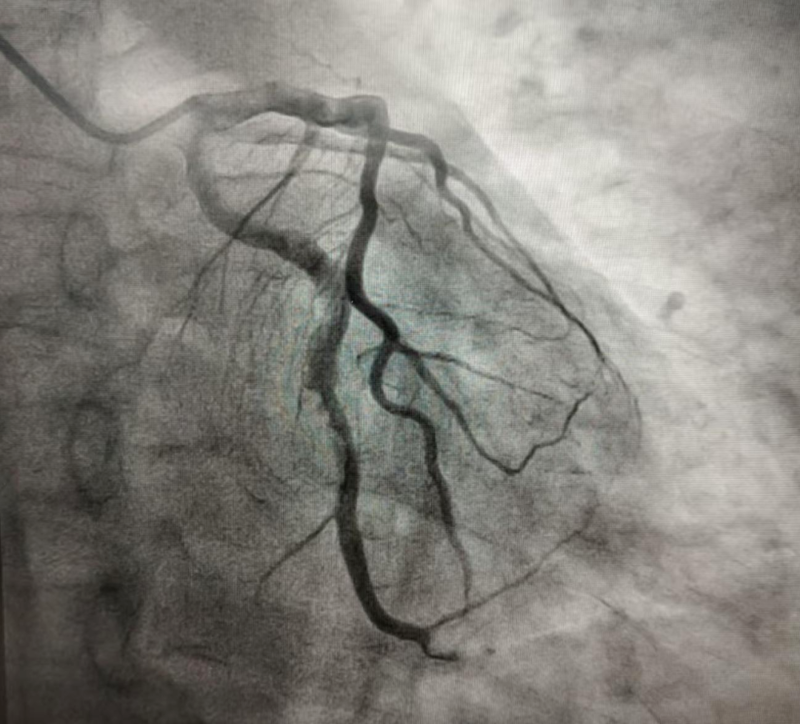

2024年10月的某天,患者程某某因胸悶兩天,前來惠州市中心人民醫(yī)院博羅分院(博羅縣人民醫(yī)院)心血管內(nèi)科就診。經(jīng)診查,診斷為冠心病、急性非ST段抬高型心肌梗死 KillipI級,GRACE評分122分,危險分層高危。行冠脈造影示回旋支遠段近端見大量血栓影、狹窄90%,遠段遠端見大量血栓影、狹窄100%閉塞,前向血流TIMI0級(圖1)。心血管內(nèi)科團隊予為患者行PTCA和血栓抽吸術,復查造影顯示:回旋支遠段近端血栓無變化,遠段遠端血栓消失(圖2)。考慮血栓負荷重,回旋支遠段近端暫不宜行支架置入術,擬給予抗栓治療后擇期復查冠脈造影。

4天后,患者復查冠脈造影示回旋支中段可見可疑夾層征象,前向血流TIMI 3級(圖3)。